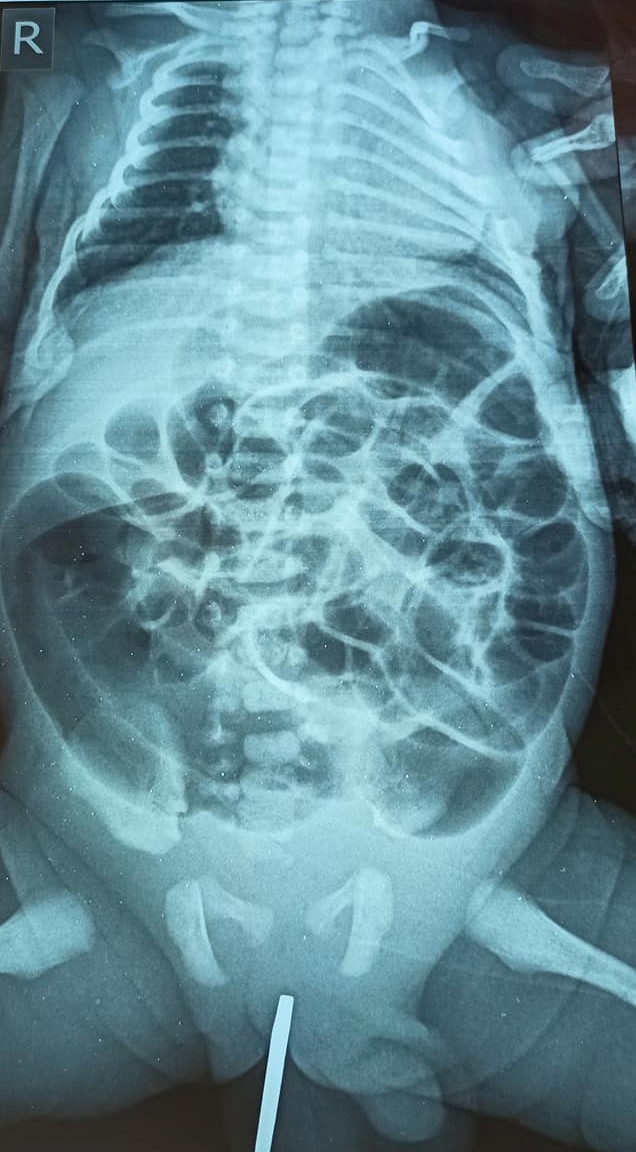

Ховд аймгийн Бүсийн оношилгоо, эмчилгээний төвийн хамт олон ЭХЭМҮТ-ийн Хүүхдийн ерөнхий мэс заслын тасгийн эрхлэгч Л.Ганбаяр эмчтэй телемедицинээр холбогдон Булган сумын Нэгдсэн эмнэлэгт 2800 грамм жинтэй төрсөн, төрөлхийн хошного, шулуун гэдэс битүү эмгэг бүхий нярайд анхан шатны мэс заслын эмчилгээг амжилттай хийсэн юм. Нярайн мэс заслын эмчилгээний бүрэлдэхүүнд Ховд аймгийн хүүхдийн мэс заслын эмч Б.Батболд, мэс заслын эмч Б.Сүхнаран, мэдээгүйжүүлэгч эмч, Б.Анхбаяр, нярайн эмч Ц.Солонго, хүүхдийн эмч Г.Хулан, мэс заслын сувилагч Б.Баярхүү, мэдээгүйжүүлэгч сувилагч Т.Баярцэцэг, нярайн сувилагч Д.Одгэрэл, үйлчлэгч М.Баасанхүү нар ажилласан байна. Дөнгөж төрсөн нярайд мэс засал хэрхэн хийсэн талаар Ховд аймгийн хүүхдийн мэс заслын эмч Б.Батболдтой ярилцлаа.

-Төрөлхийн хошного, шулуун гэдэс битүү эмгэгийн мэс заслыг хоёр дахь удаагаа хийж байна. Анхныхыг нь өнгөрсөн жил хийж байлаа. Маш ховор тохиолддог, хүнд өвчин.

Л.Ганбаяр эмчтэй телемедицинээр холбогдож хамтын хүчээр мэс засал хийлээ. Мөн Ховд аймгийн Бүсийн оношилгоо эмчилгээний төвийн найман эмч, сувилагчтай хамтран мэс заслаа амжилттай хийсэн. Мэс засал 90 минут үргэлжилсэн.